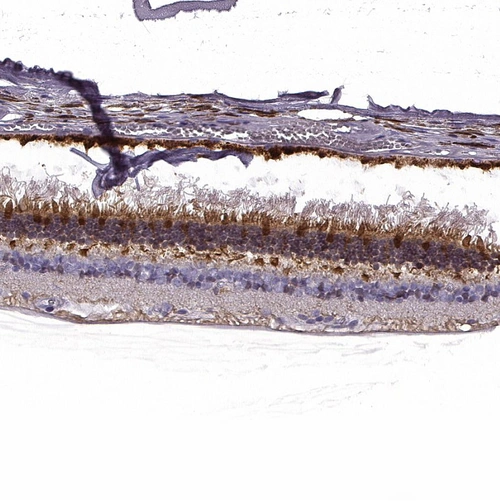

Immunohistochemical staining of human retina shows moderate to strong positivity in photoreceptor layer as well as outer plexiform layer.

HPA005561

guanylate cyclase activator 1A (retina)

Anti-GUCA1A Antibody

Polyclonal Antibody against HUMAN GUCA1A